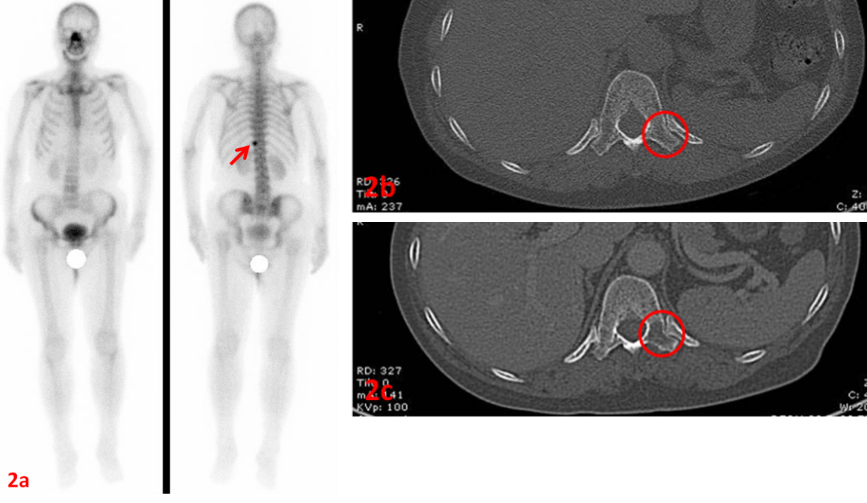

老年女性,右肺腺癌。ECT示T11左側(cè)橫突(圖2a紅箭)代謝異常,考慮骨轉(zhuǎn)移,同期CT檢查未見明顯異常(圖2a紅圈)。

2個月后復(fù)查CT示T11左側(cè)橫突溶骨性破壞(圖2c紅圈)。